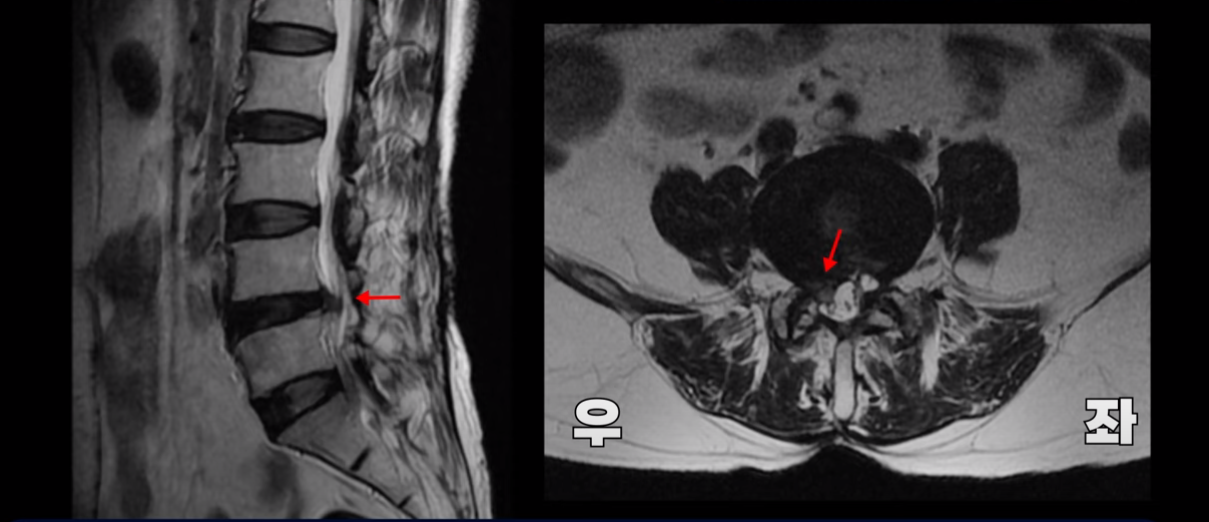

이 환자분 MRI를 보면 보시다시피 4번, 5번 디스크 파열로 오른쪽으로 심하게 밀려 나와있습니다.

그래서 이분은 오른쪽 엉덩이와 오른쪽 다리에 심한 방사통이 있으셨습니다.

여기 보시다시피 과거에 수술 받은 결과로 뒤쪽의 후관절 뼈 일부가 없어진 것이 보입니다.